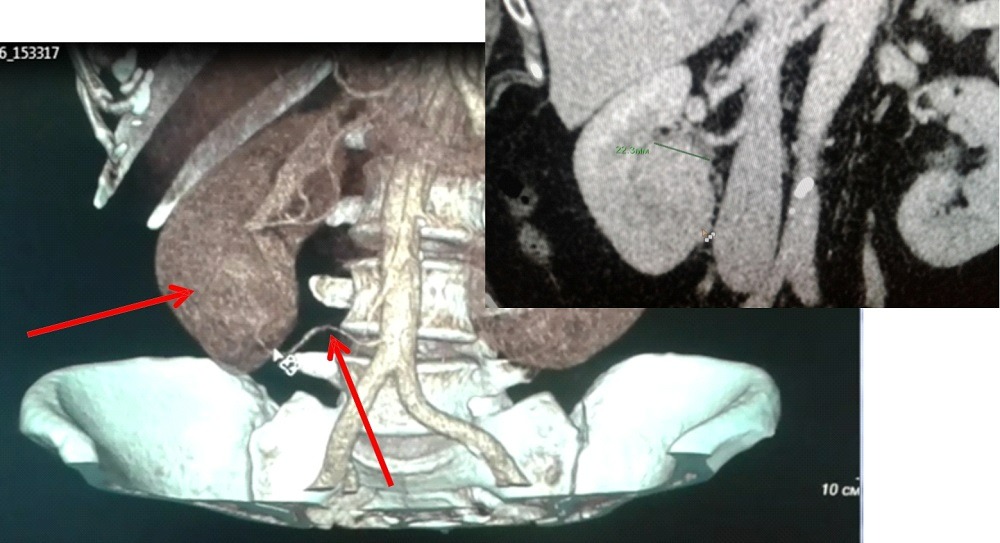

В случае, если опухоль распространяется в просвет почечной вены и/или в нижнюю полую вену, лапароскопический вариант операции возможен, однако он чаще, чем обычно, требует перехода на большой разрез при технических сложностях.

Удаление метастазов (метастазэктомия)

У около 25% больных раком почки на момент диагностики имеется распространение (метастазы) заболевания на другие органы. Наиболее часто к ним относятся легкие, кости, печень и головной мозг. В некоторых случаях при такой ситуации может помочь оперативное лечение. Наиболее часто оно может применяться в случаях, если имеется единичный метастаз, который может быть хирургически удален, либо в случаях, когда удаление метастаза может облегчить симптомы болезни, такие как боль.